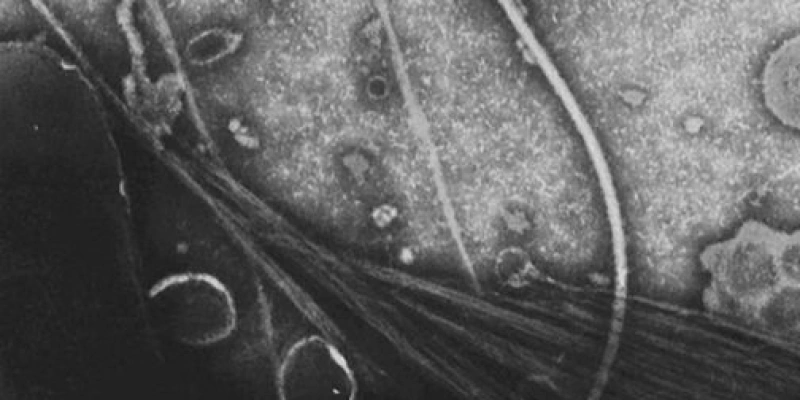

Causado pela enterotoxina do bacilo Vibrio cholerae O1, ou O139, o cólera compõe o quadro das doenças diarreicas agudas. A maioria das pessoas infectadas não apresenta sintomas (cerca de 75%). Daquelas que ficam doentes, a maioria tem sintomas leves ou moderados. Já a forma grave afeta de 10% a 20%, podendo levar a complicações graves e até à morte se não tratada rapidamente.

Vibrio cholerae O1: é uma bactéria e pode ser encontrada naturalmente em diversos ecossistemas. Pode ser encontrada na água, pois faz parte da vida microscópica nos oceanos e rios. Ela pode estar livre ou ligada a animais como crustáceos, moluscos, peixes e algas, bem como em superfícies não vivas, como o lixo nas praias.